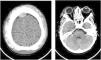

Laboratory tests showed hemoglobin (Hb) of 7.8 g/dL; leukocytes 22,700/mm3, without left shift; platelets 369,000/mm3; reticulocytes 13 % and with normal coagulogram. A CT scan of the skull showed a small hyperdense extra-axial collection located in the right parietal high convexity with no evidence of bone fractures or midline shift.

A new CT scan of the skull showed a epidural hematoma in the right frontoparietal high convexity, with 10 mm thickness, pressing the adjacent parenchyma, associated with dense subperiosteal collections near both orbits, two on the right and one on the left, with thicknesses of 11 mm and 10 mm respectively, promoting proptosis of the eyeballs (Figure 1).

Neurosurgical evaluation was requested and magnetic resonance imaging of the skull confirmed the frontoparietal epidural hematomas and extraconal intraorbital hematomas, as well as signs of bone infarction and diffuse heterogeneity of skull's bone marrow. A hypothesis of non-traumatic spontaneous epidural hematoma related to sickle cell anemia was made.